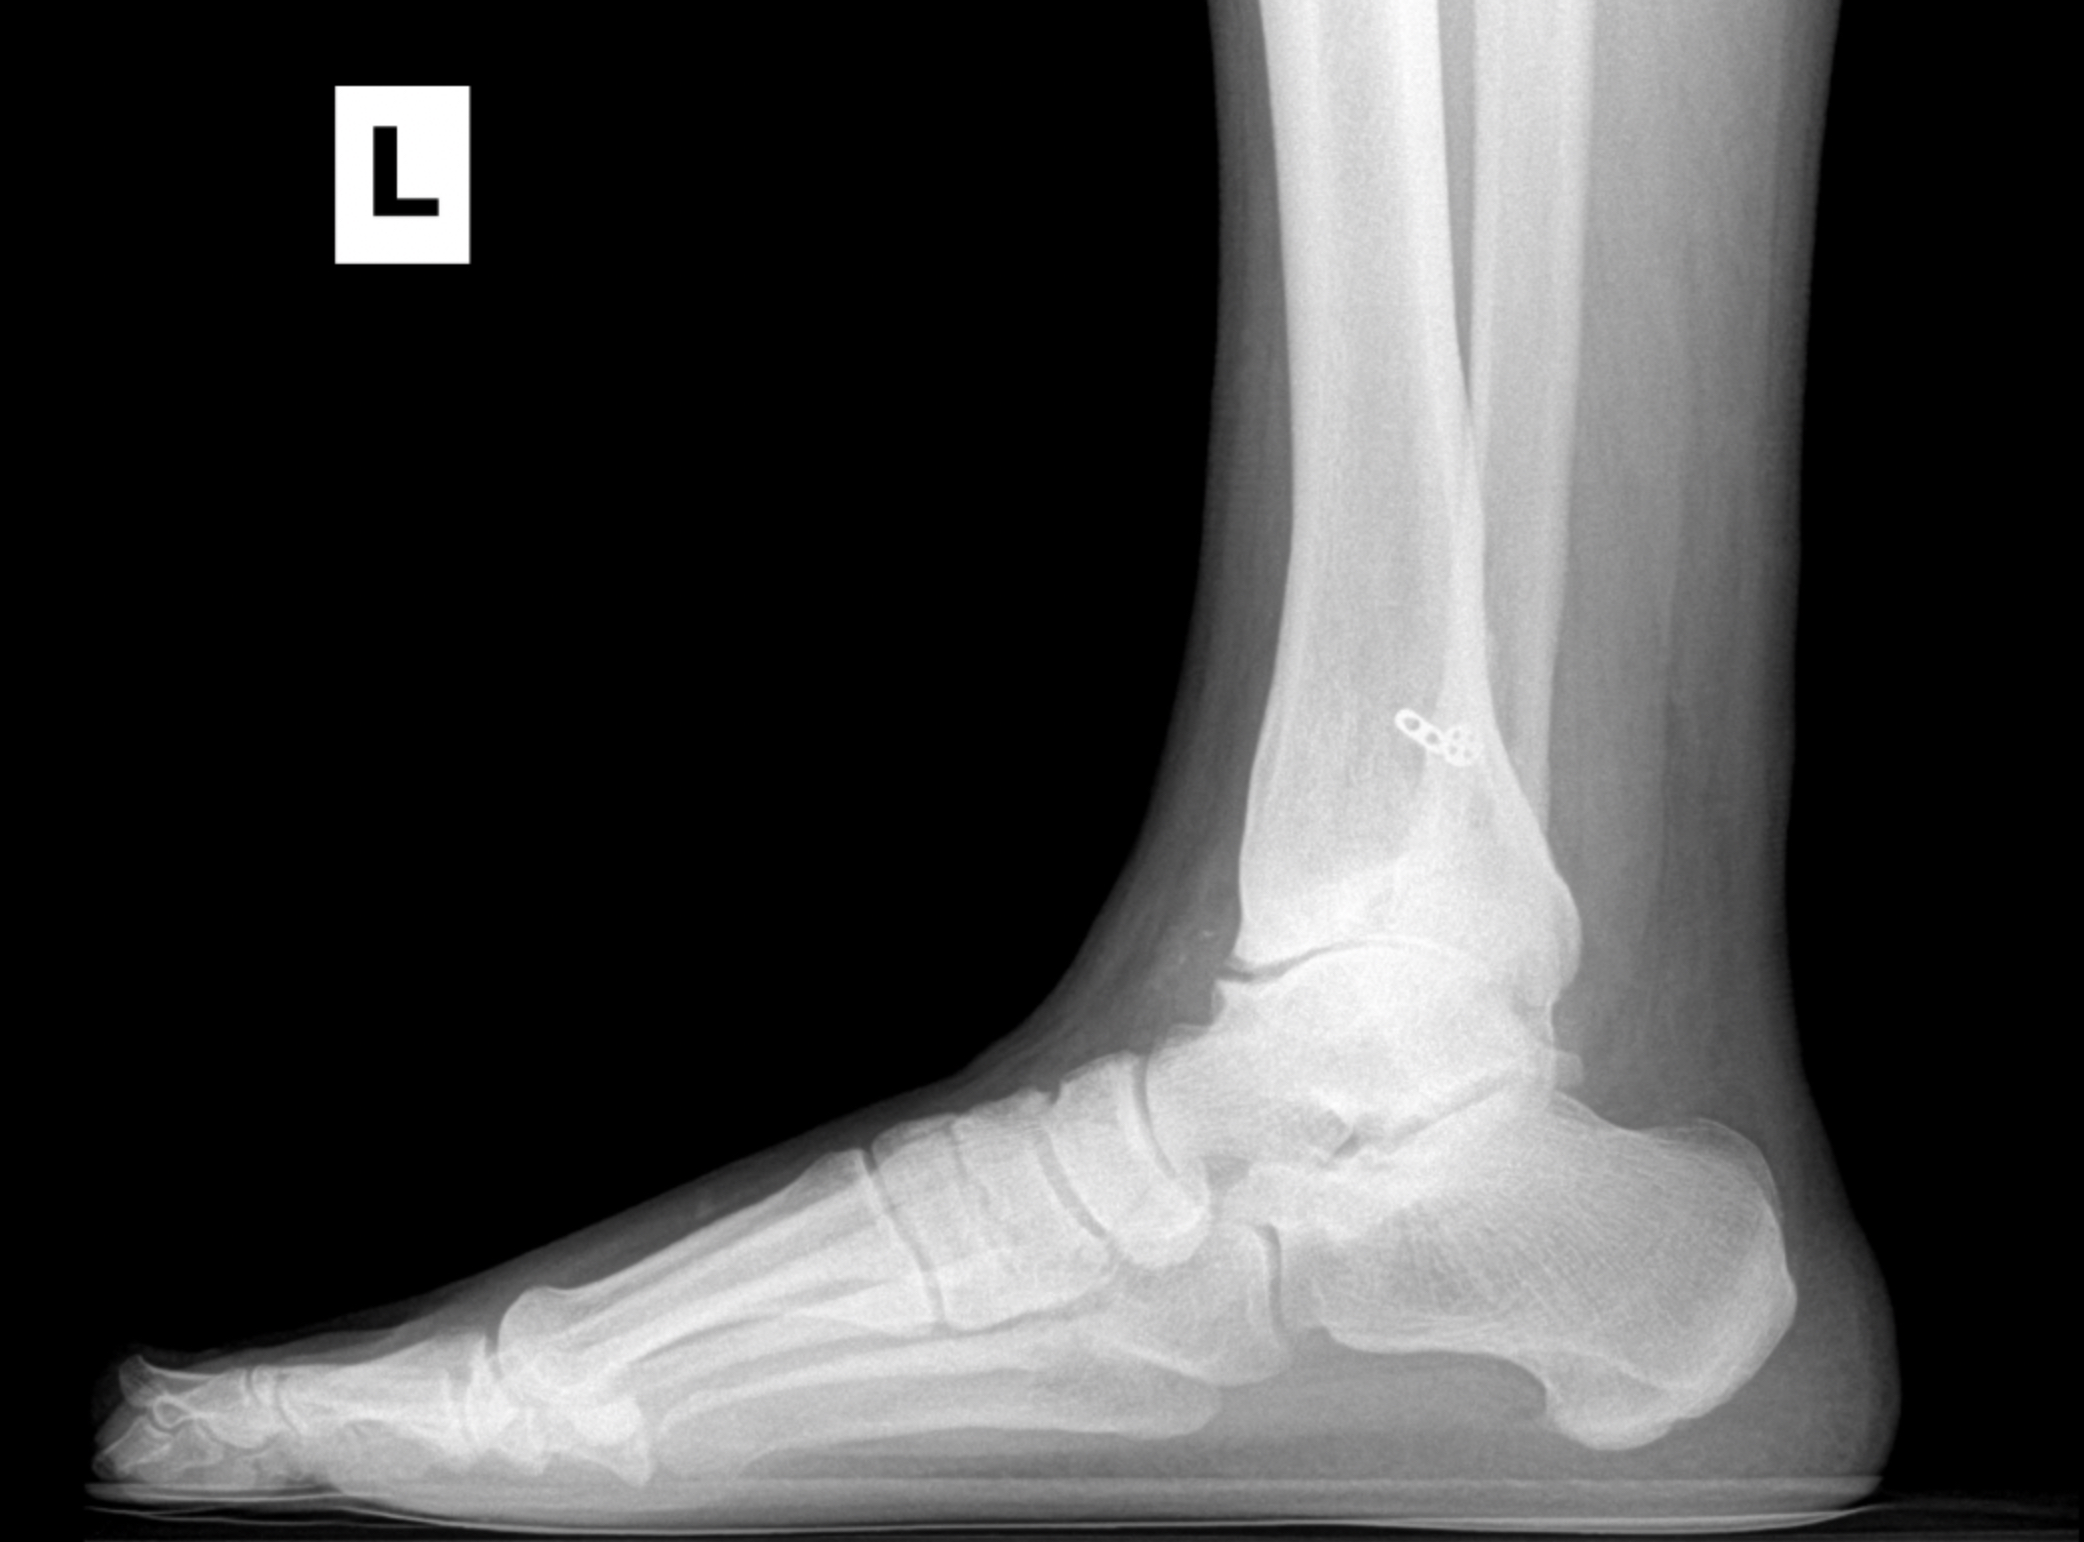

Foot & Ankle Replacement

Coming Soon